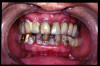

CM Desgaste por bruxismo, presencia de cálculo